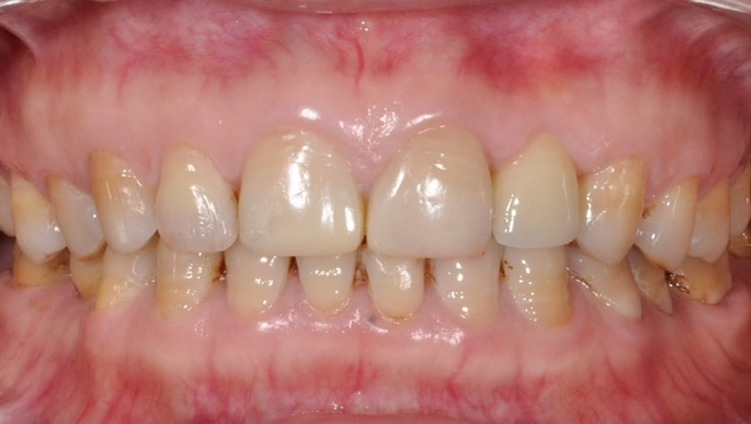

Phục hồi trên implant tại vùng thẩm mỹ như răng thật tại Nha Khoa Như Ngọc (21 Trần quang diệu, Hà Nội).